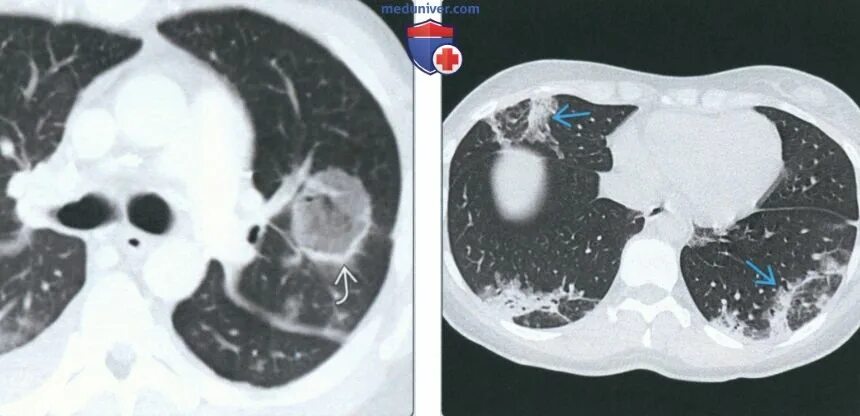

Гипостатические изменения кт